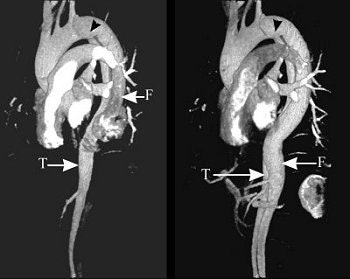

Aortic dissection assessment, before (above) and after (below) surgery.